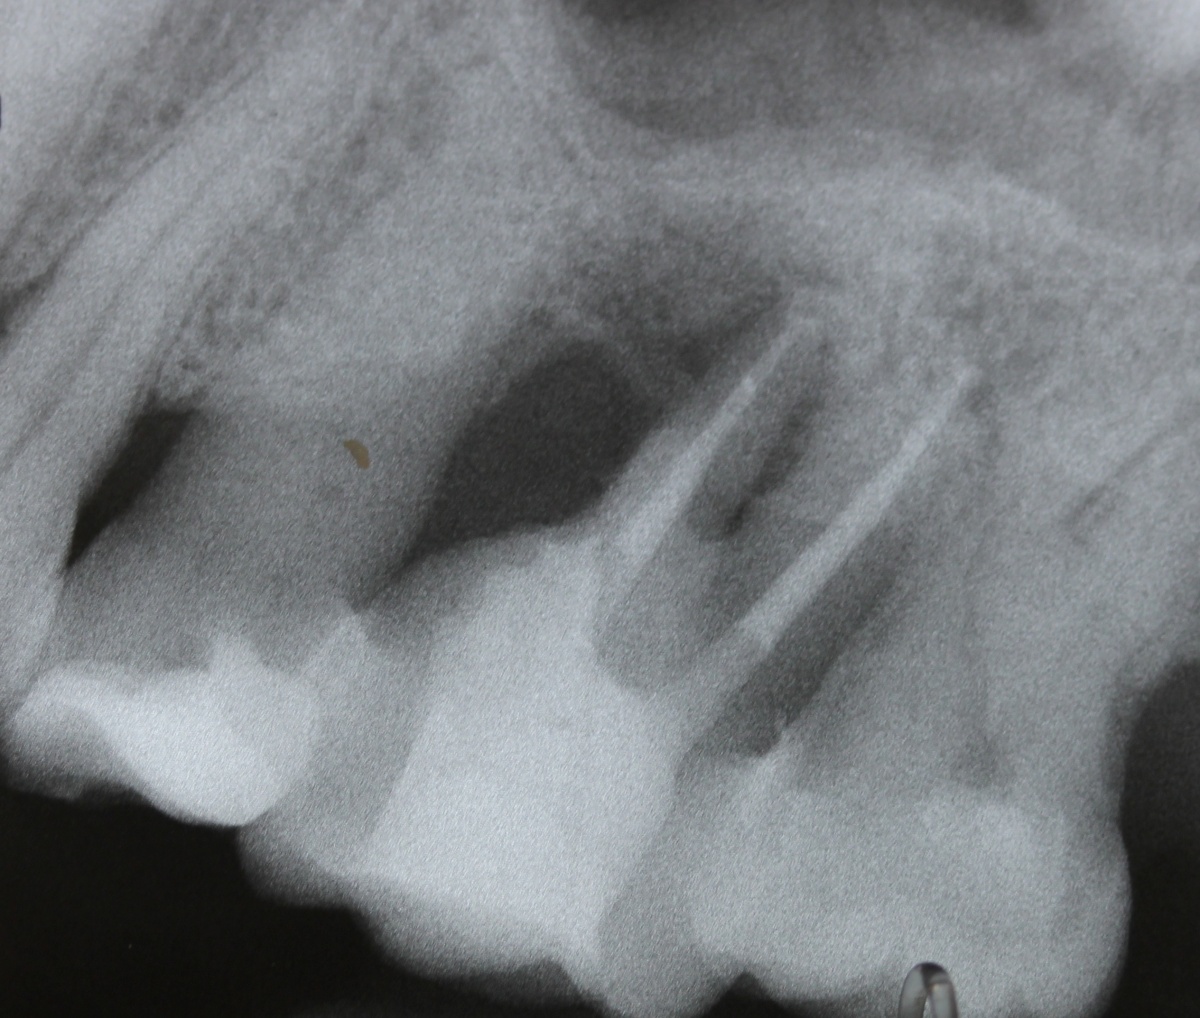

Eine Schnittstelle zu den bereits ausgeführten parodontalen Voraussetzungen des Zahnerhalts ergibt sich bei kombinierten Paro-Endo-Läsionen beziehungsweise Endo-Paro-Läsionen. Zeigen konservative Behandlungsansätze bei den meisten dieser Befunde gute Ergebnisse, ist bei einem lokal ausgeprägten Knochenabbau zumeist die chirurgische Intervention zum Zahnerhalt notwendig (Abb. 11 und 12). Wichtig dabei ist die Unterscheidung der primären Ursache (primär endodontische oder primär parodontale Ätiologie) der Läsion und einem dieser Ursache angepasstem Behandlungsprotokoll.